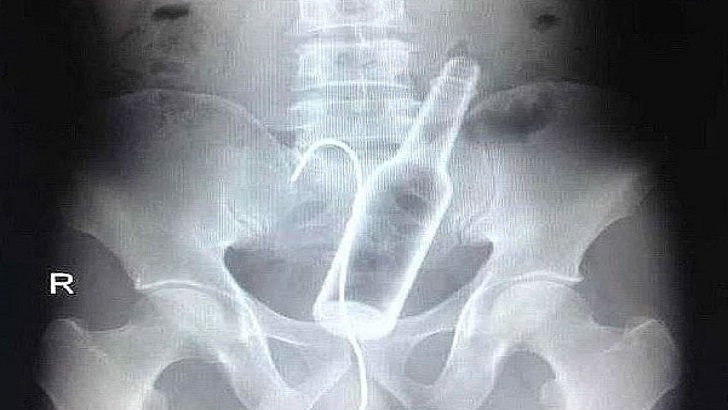

2-) Bu fotoğrafta da cam bardağı sokmuş bir hasta görüyoruz. Şanslı ki bardak içerde kırılmamış